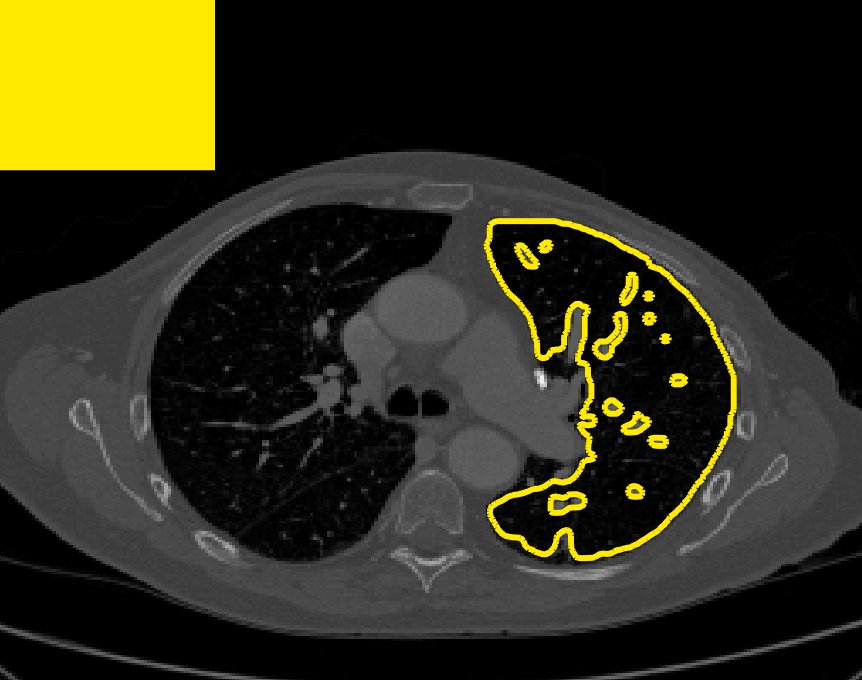

The motivation for this work comes from observing contradictions in using piecewise-constant intensity fitting terms in selective segmentation. Whilst good results are possible with this approach, the exceptional cases lead to severe limitations in practice. This is quite common in medical imaging as demonstrated in Fig. 1, where the target foreground has a low intensity. Given that the corresponding background includes large regions of low intensity, the optimal average intensities for this segmentation problem are and . For cases where , we see that by (1), almost everywhere in the domain . This means that it is very difficult to achieve an adequate result, without an over-reliance on the user input or parameter selection.

for and as defined in (33). This is consistent with respect to the intensities of the observed object and the concept of selective segmentation. In Fig. 3 we see the difference between CV and the proposed fitting terms for given user input on a CT image. For the CT image, the CV fitting terms are near 0 within the target region. This is despite there being a distinct homogeneous area with good contrast on the boundary. This illustrates the problem we are aiming to overcome. With the proposed fitting term this phenomenon should be avoided in cases like this. By defining as in (33) there is no contradiction if the foreground and background intensities of the target region are similar.